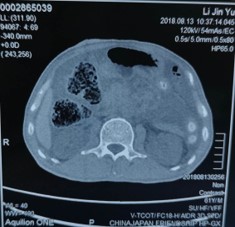

2018年8月13日胸腹盆CT:双肺陈旧病变,双侧胸腔少量积液,胆囊结石,直肠术后改变,右侧腹部造瘘术后,肝转移瘤可能,腹盆腔大量积液,腹膜转移可能。皮下水肿,睾丸鞘膜积液。